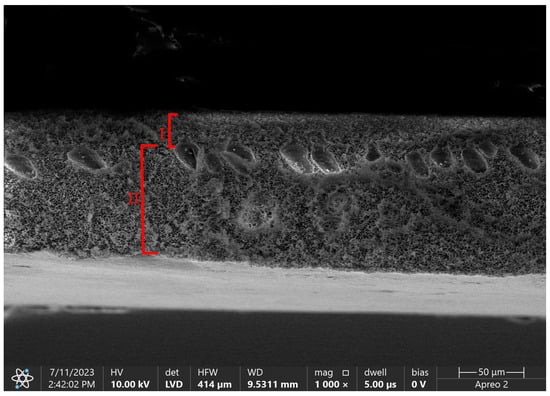

5. Methods of Anticoagulation

6.4. Scanning Electron Microscopy